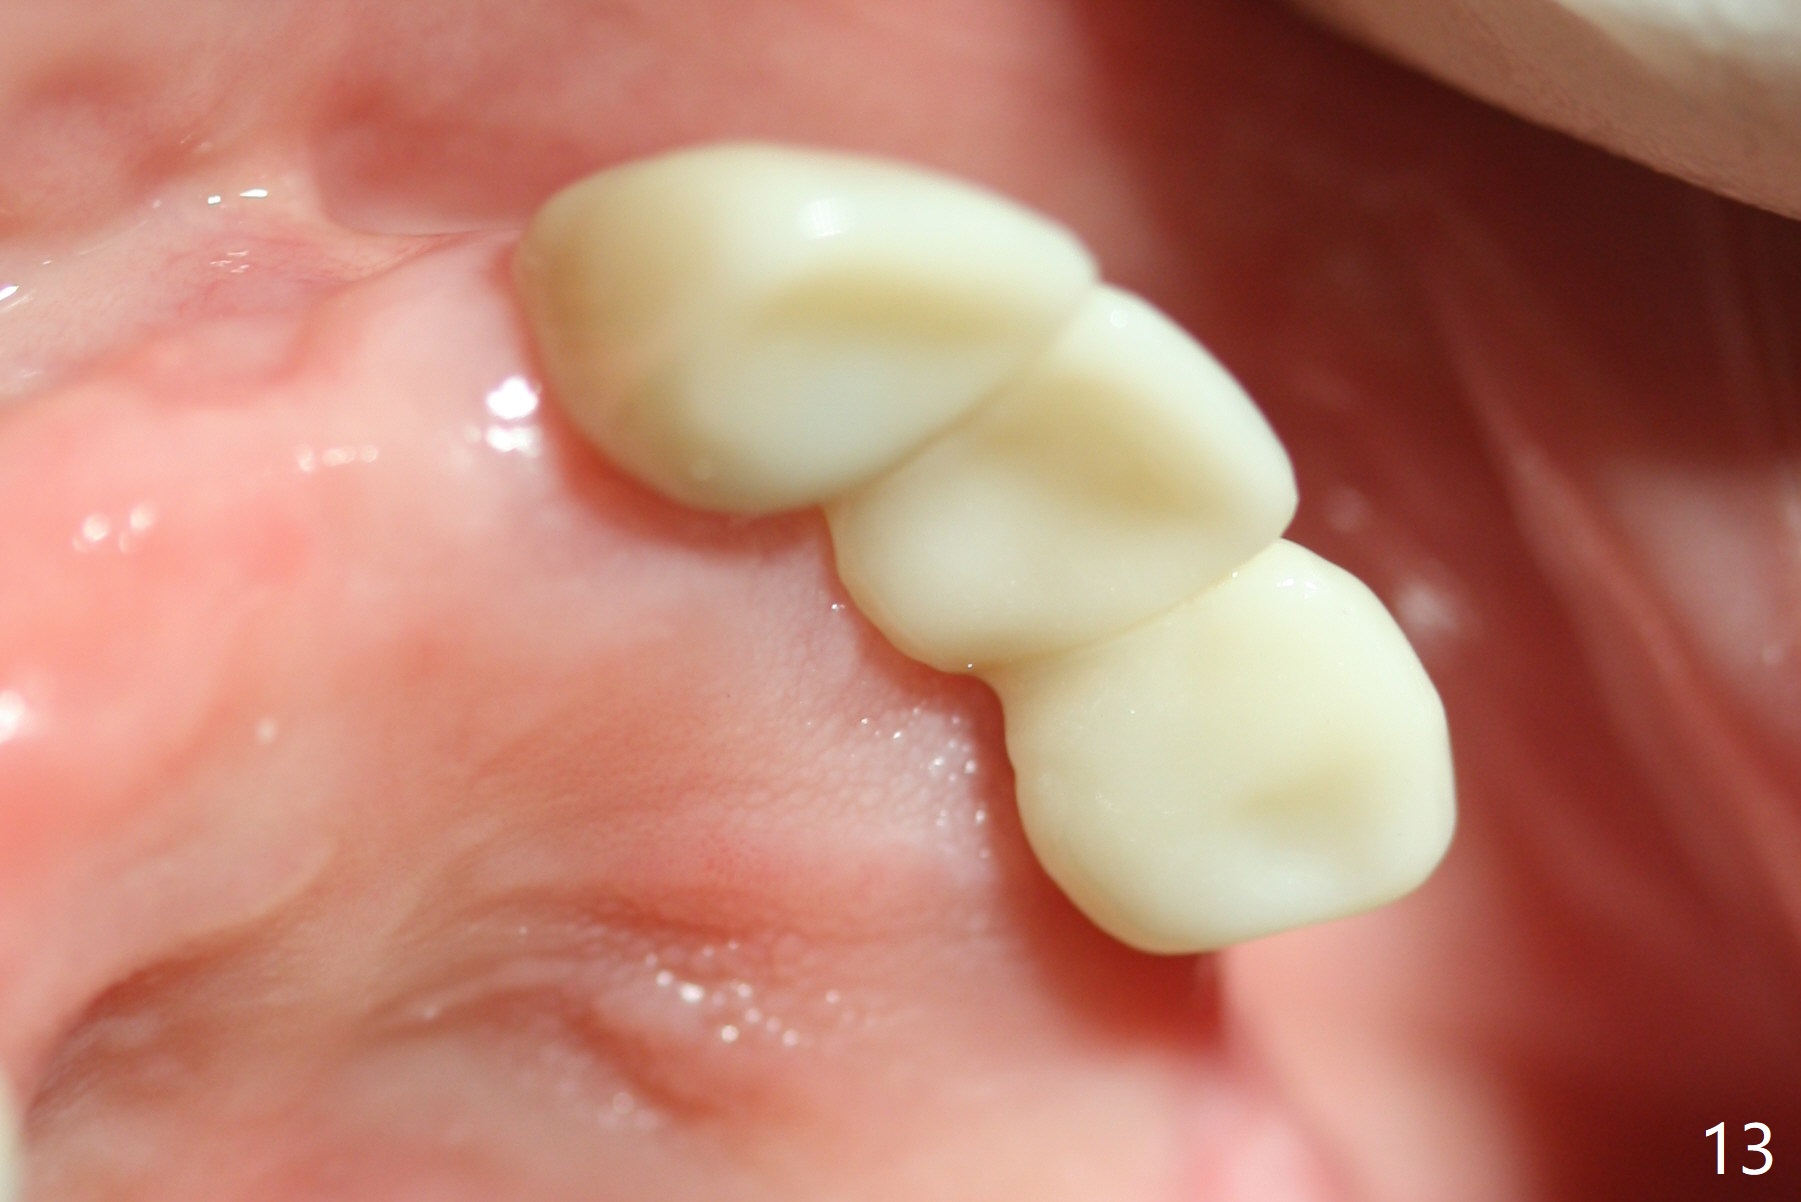

Incision reveals that the ridge at #9 and 11 is narrower than expected. A 3x14 mm 15º 1 piece implant is placed at the site of #9, while a 3x17 mm straight 1-piece one is placed at #11 (Fig.1,4). Insertion torques at #9 and 11 are 20 and 30 Ncm, respectively. The relatively low insertion torque is partially due to osteoporosis. The 65-year-old lady also has dry mouth. Osteotomy should be underprep. The position and trajectory of the implants are dictated by the partial denture (Fig.2). After minor abutment adjustment (Fig.3), an immediate provisional bridge is fabricated. There is no interference when the partial is removed and inserted. After bone graft (Fig.4 ^) and Osteogen Membrane, the ridge (Fig.3) is wider than before. The patient returns for reline 2 months postop (Fig.5-7). In spite of insufficient oral hygiene, the gingiva remains healthy around the implants. To form distinct papillae, acrylic should be added to (Fig.8 yellow line) and removed from (hushed area) the individual provisional crowns. One month after provisional modification (Fig.10, as compared to Fig.5), the pontic recipient site is concave (Fig.11) and becomes less concave after cord packing and abutment trimming. When the provisional bridge is reseated after impression (Fig.12), the pontic recipient site must be blanched again. Please trim the pontic recipient site of the model ~ .5 mm to enhance cosmetics. Water Pik has been used since surgery, but it may be related to loss of bone graft 3.5 months postop (Fig.9 *). One month post cementation, the patient has complained of pain when water pik is irrigating the gingiva palatal to the FPD, apparently in association with denture-related Candidiasis. Two weeks of use of Mycostatin Oral Suspension, peri-implantitis or peri-implant mucositis-like signs and symptoms disappear (Fig.13). CBCT taken 6 months postop confirms that the implants appear to be have been placed in the bone (14,15). The FPD appears to be loose 2.5 years post cementation.